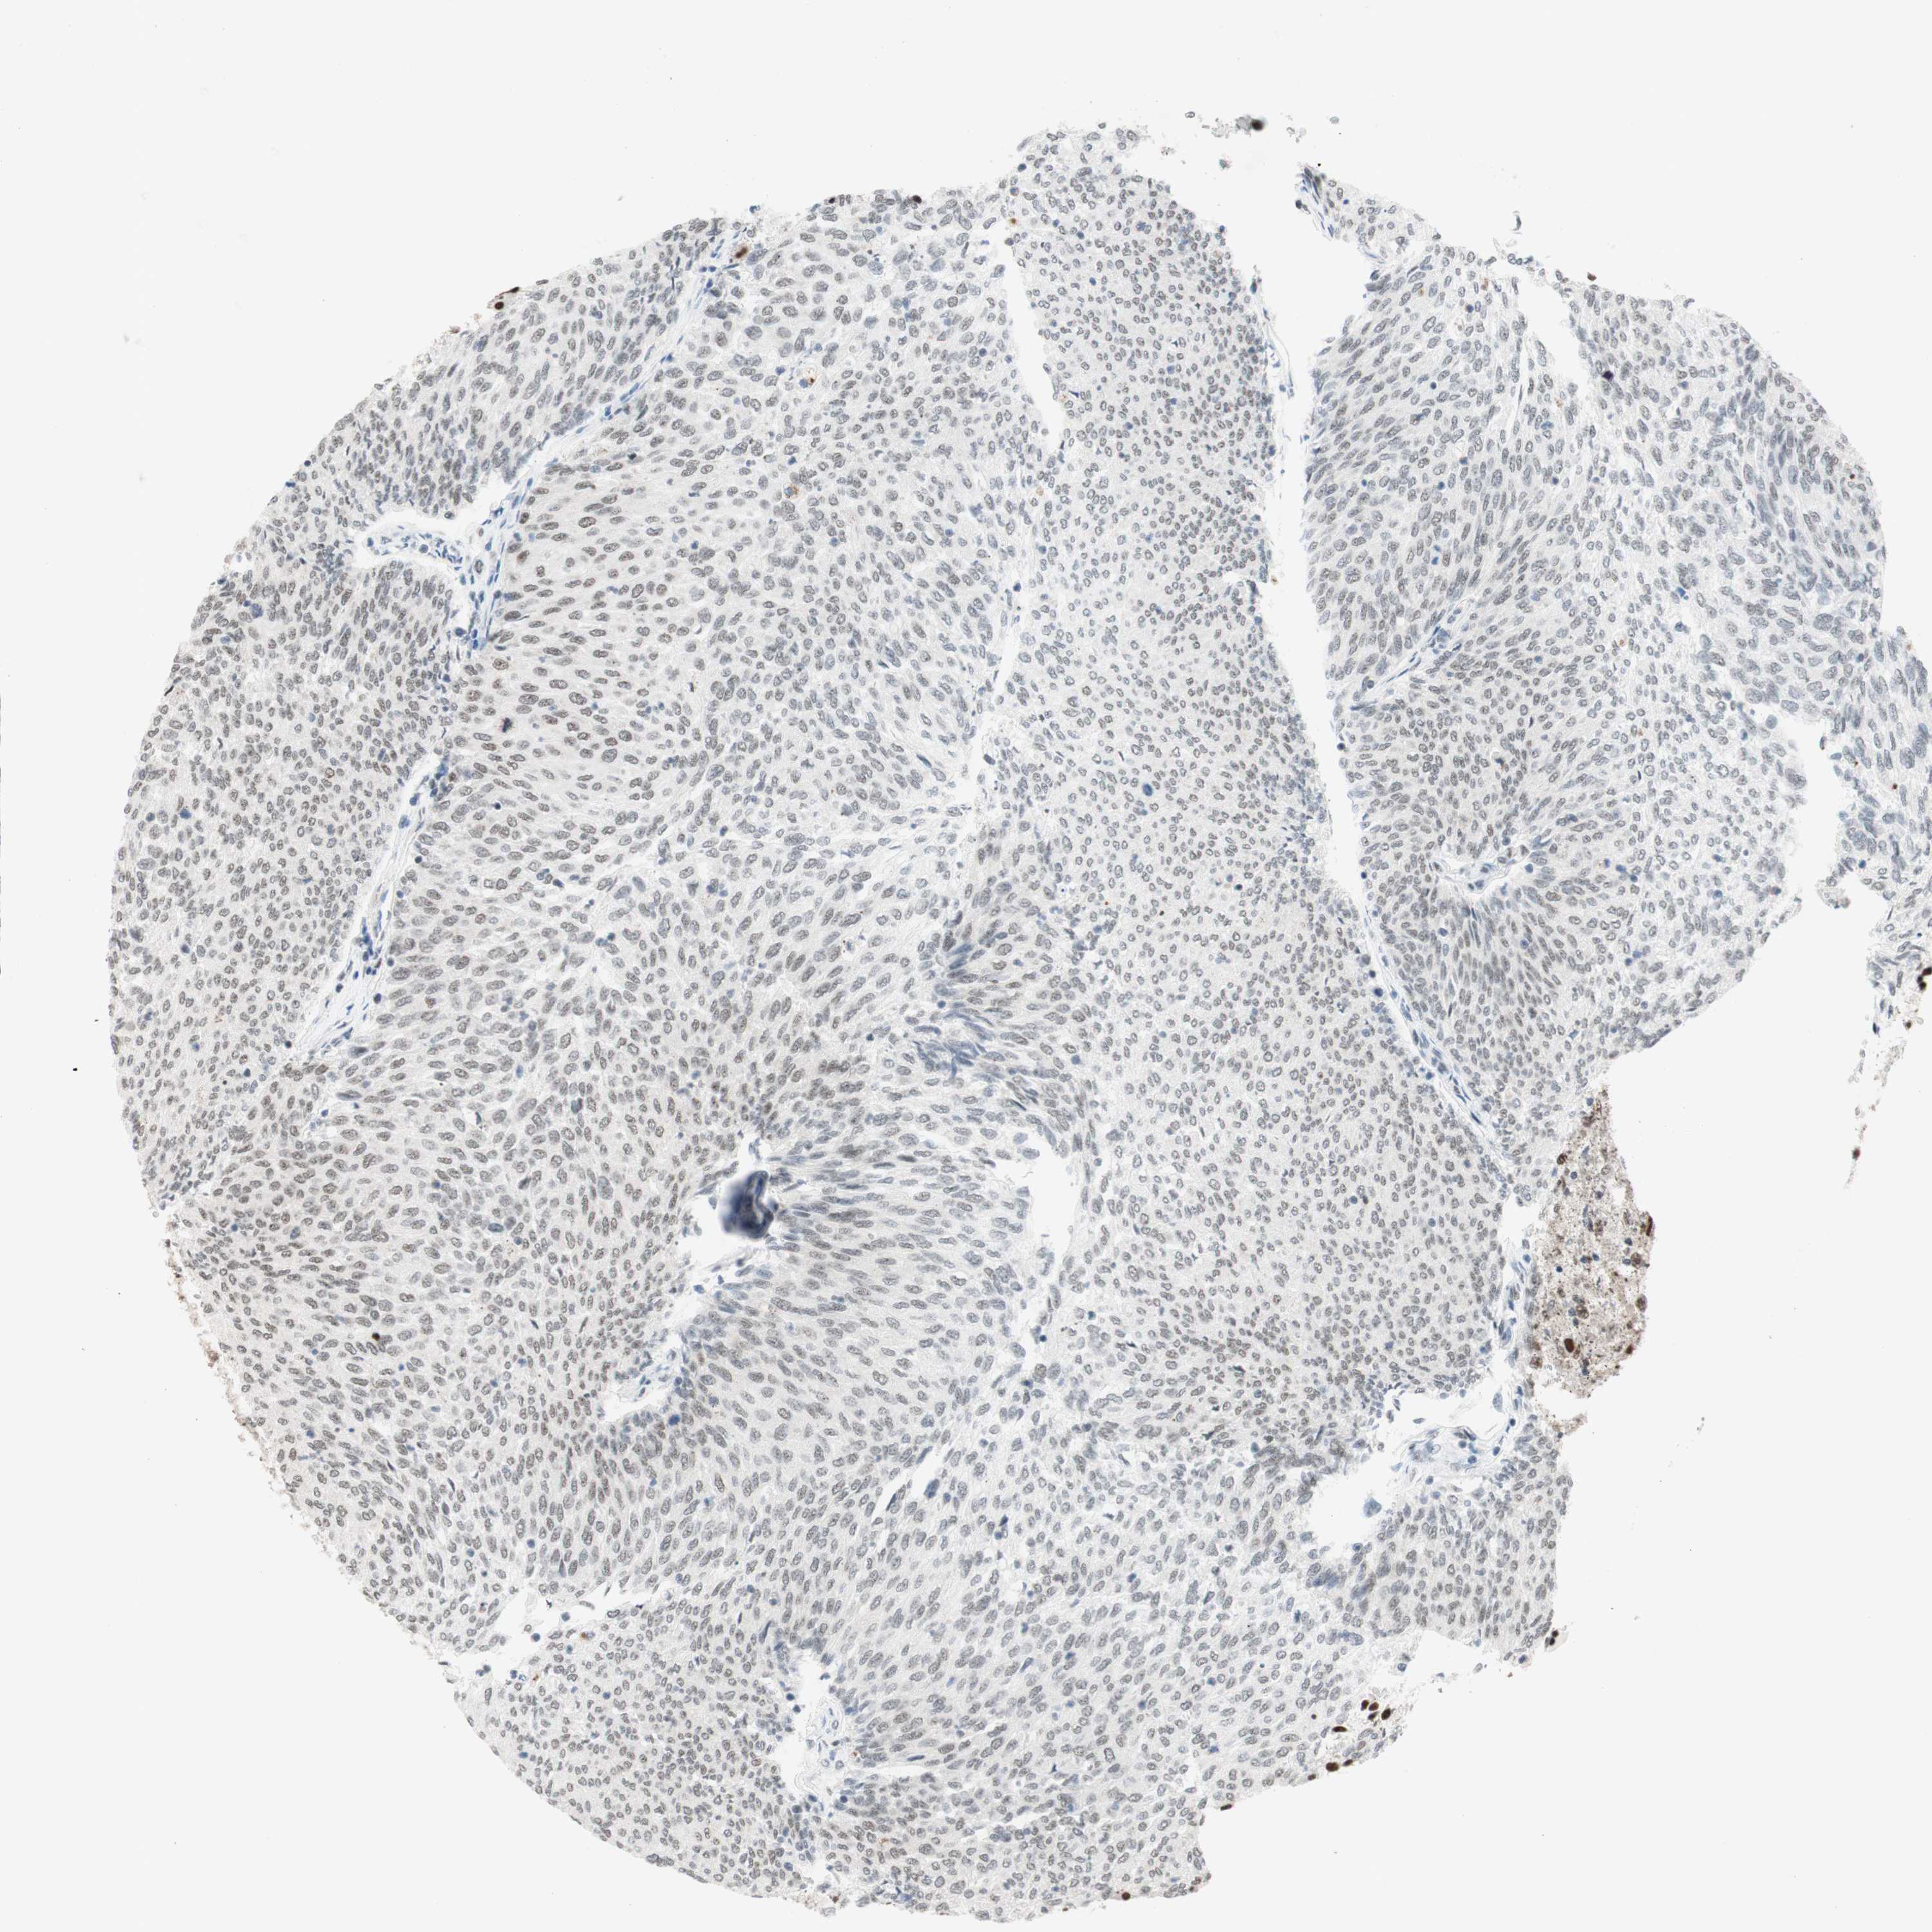

UROTHELIAL CANCER - Protein expressioni

A mouse-over function shows sample information and annotation data. Click on an image to view it in a full screen mode. Samples can be filtered based on level of antibody staining by selecting one or several of the following categories: high, medium, low and not detected. The assay and annotation is described here.

Note that samples used for immunohistochemistry by the Human Protein Atlas do not correspond to samples in the TCGA dataset.

Antibody stainingi

Antibody staining in the annotated cell types in the current human tissue is reported as not detected, low, medium, or high, based on conventional immunohistochemistry profiling in selected tissues. This score is based on the combination of the staining intensity and fraction of stained cells.

Each image is clickable and will lead to virtual microscopy that enables deeper exploration of all samples and also displays staining intensity scores, fraction scores and subcellular localization as well as patient and tissue information for each sample.

Antibody HPA038051

Antibody HPA059070

Antibody CAB012448

Staining

High

Medium

Low

Not detected

Intensity

Strong

Moderate

Weak

Negative

Quantity

>75%

75%-25%

<25%

None

Location

Nuclear

Cytoplasmic/membranous

Cytoplasmic/membranous,nuclear

Urothelial carcinoma, High grade

Urothelial carcinoma, Low grade

Urothelial carcinoma, NOS